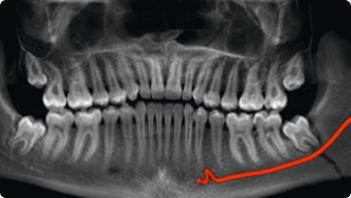

Impacted Tooth

OPG Reporting